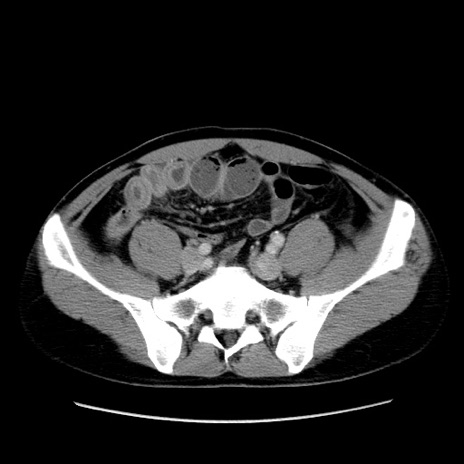

症例4(横断像)

【症例】30歳代男性

【主訴】腹痛、嘔吐

【現病歴】昨晩から突然の腹痛あり、その後嘔吐、軟便も出現。腹痛が改善しないため救急搬送となる。2日前にしめ鯖の食事歴あり。

【身体所見】意識清明、苦悶様、BP 135/90mmHg、BT 35.7℃、腹部:平坦、やや硬、心窩部〜臍部に自発痛、圧痛あり、筋性防御+、反跳痛-

【データ】WBC 8100、CRP 0.57